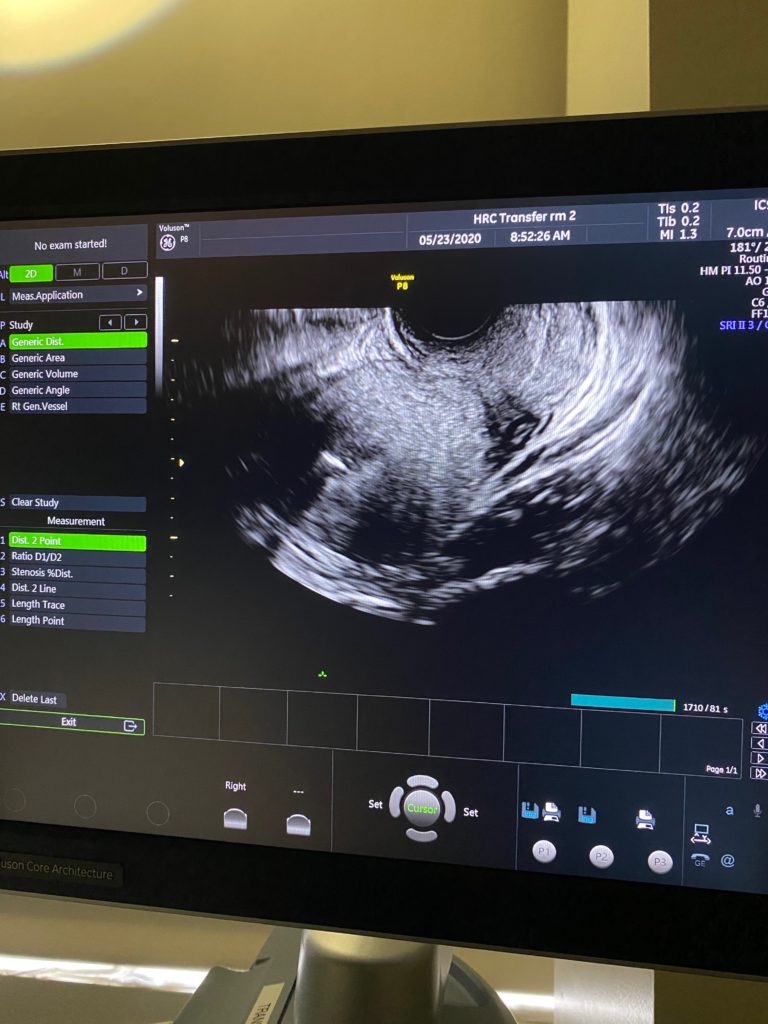

代母按照常规会再移植前到试管诊所做最后一次检查,确认身体指标都符合条件。但是这个代母在检查的时候发现子宫里有少量积水,医生都很谨慎,一旦遇到有积水,就是不能移植,有失败的风险。所以医生要求移植当天再检查一次,如果还是有积水就取消移植,如果积水消失,就会照常移植。客人和我们都很担心。

2020年5月23

由于疫情期间,诊所只允许代母一个人进去移植,我们就没办法陪同移植。今天医生又检查了一下,一切都正常,没有积水了。可以移植。移植很顺利,结束后,就回酒店休息了。